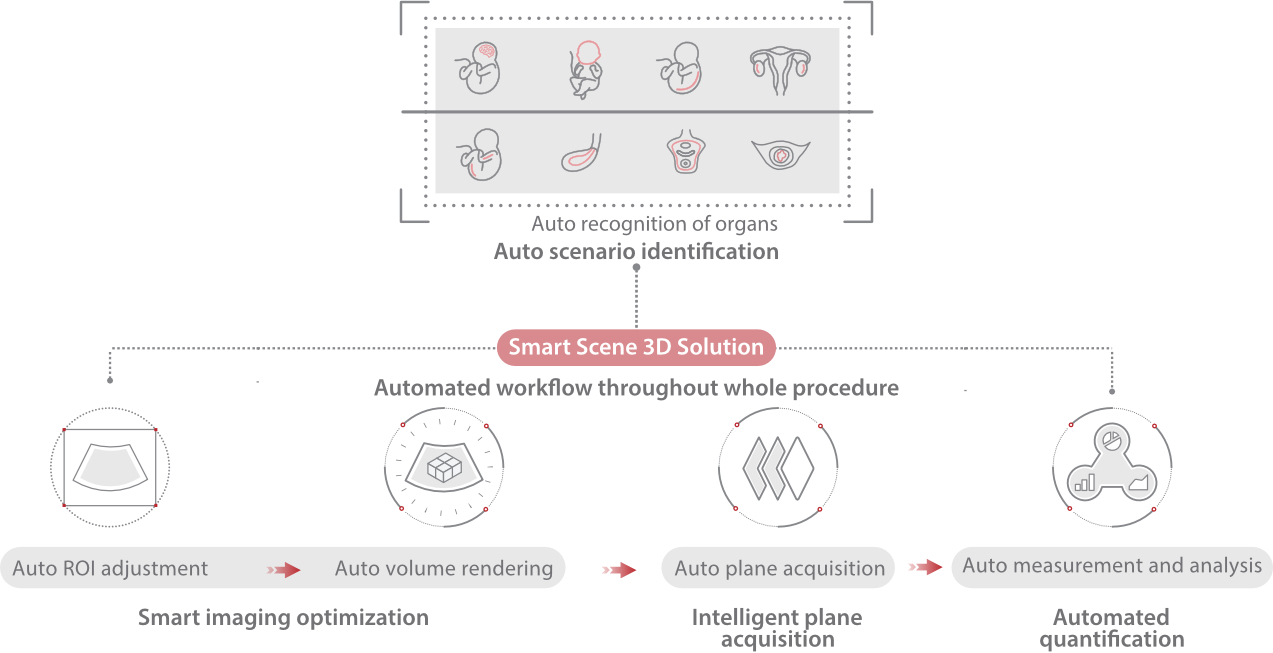

Informa??es abrangentes adaptadas aos cenƔrios

Por meio da combina??o de algoritmos avan?ados e do conhecimento especĆfico da regi?o, a inovadora solu??o Smart Scene permite a identifica??o automĆ”tica das caracterĆsticas do tecido e fornece diagnĆ³stico especĆfico dos Ć³rg?os com informa??es completas. Com base na identifica??o automĆ”tica de cenĆ”rios, a solu??o realiza n?o apenas a varredura 2D inteligente com configura??es e medidas automĆ”ticas, mas tambĆ©m oferece informa??es 3D abrangentes em todas as etapas, desde a otimiza??o de imagens volumĆ©tricas atĆ© a difĆcil obten??o de planos 2D, e a quantifica??o durante todo o procedimento. Ele ajuda a reduzir em grande parte a dependĆŖncia de habilidades clĆnicas, ao mesmo tempo que aumenta a precis?o, a confian?a e a eficiĆŖncia no diagnĆ³stico.